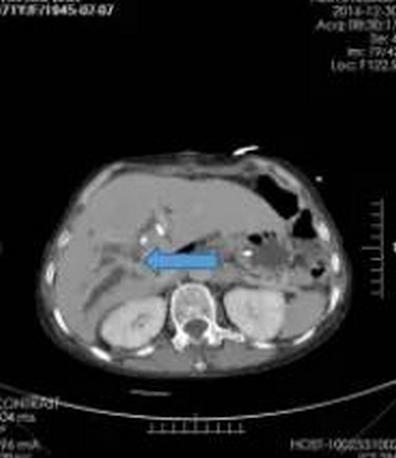

入院SCT增强扫描(箭头所指为肿瘤部位)

李晓勇教授根据病人情况多次组织科室病例讨论,认为患者年龄大,黄疸较重,肝功能较差,高胆红素血症,严重低蛋白血症。肿瘤已侵犯门静脉,不可能切除,决定先进行PTCD引流,待肝功能好转、全身营养状况改善后可行纳米刀消融手术治疗。接受PTCD术后10余天樊奶奶的黄疸减轻,身体条件较之前好转,具备了行纳米刀消融手术的条件。

手术由李晓勇教授亲自主刀,术中见肝门部质硬肿物,侵犯左右肝管,后方边界不清,无法手术切除。李晓勇教授、陈艳军副主任及郜宇医师在术中仔细分离粘连,清晰地暴露肿瘤位置,根据肿瘤大小及形态,设计进针位置,超声引导下将消融针穿刺入肿瘤内,避开门静脉,多次穿刺消融,直至肿瘤全部覆盖。